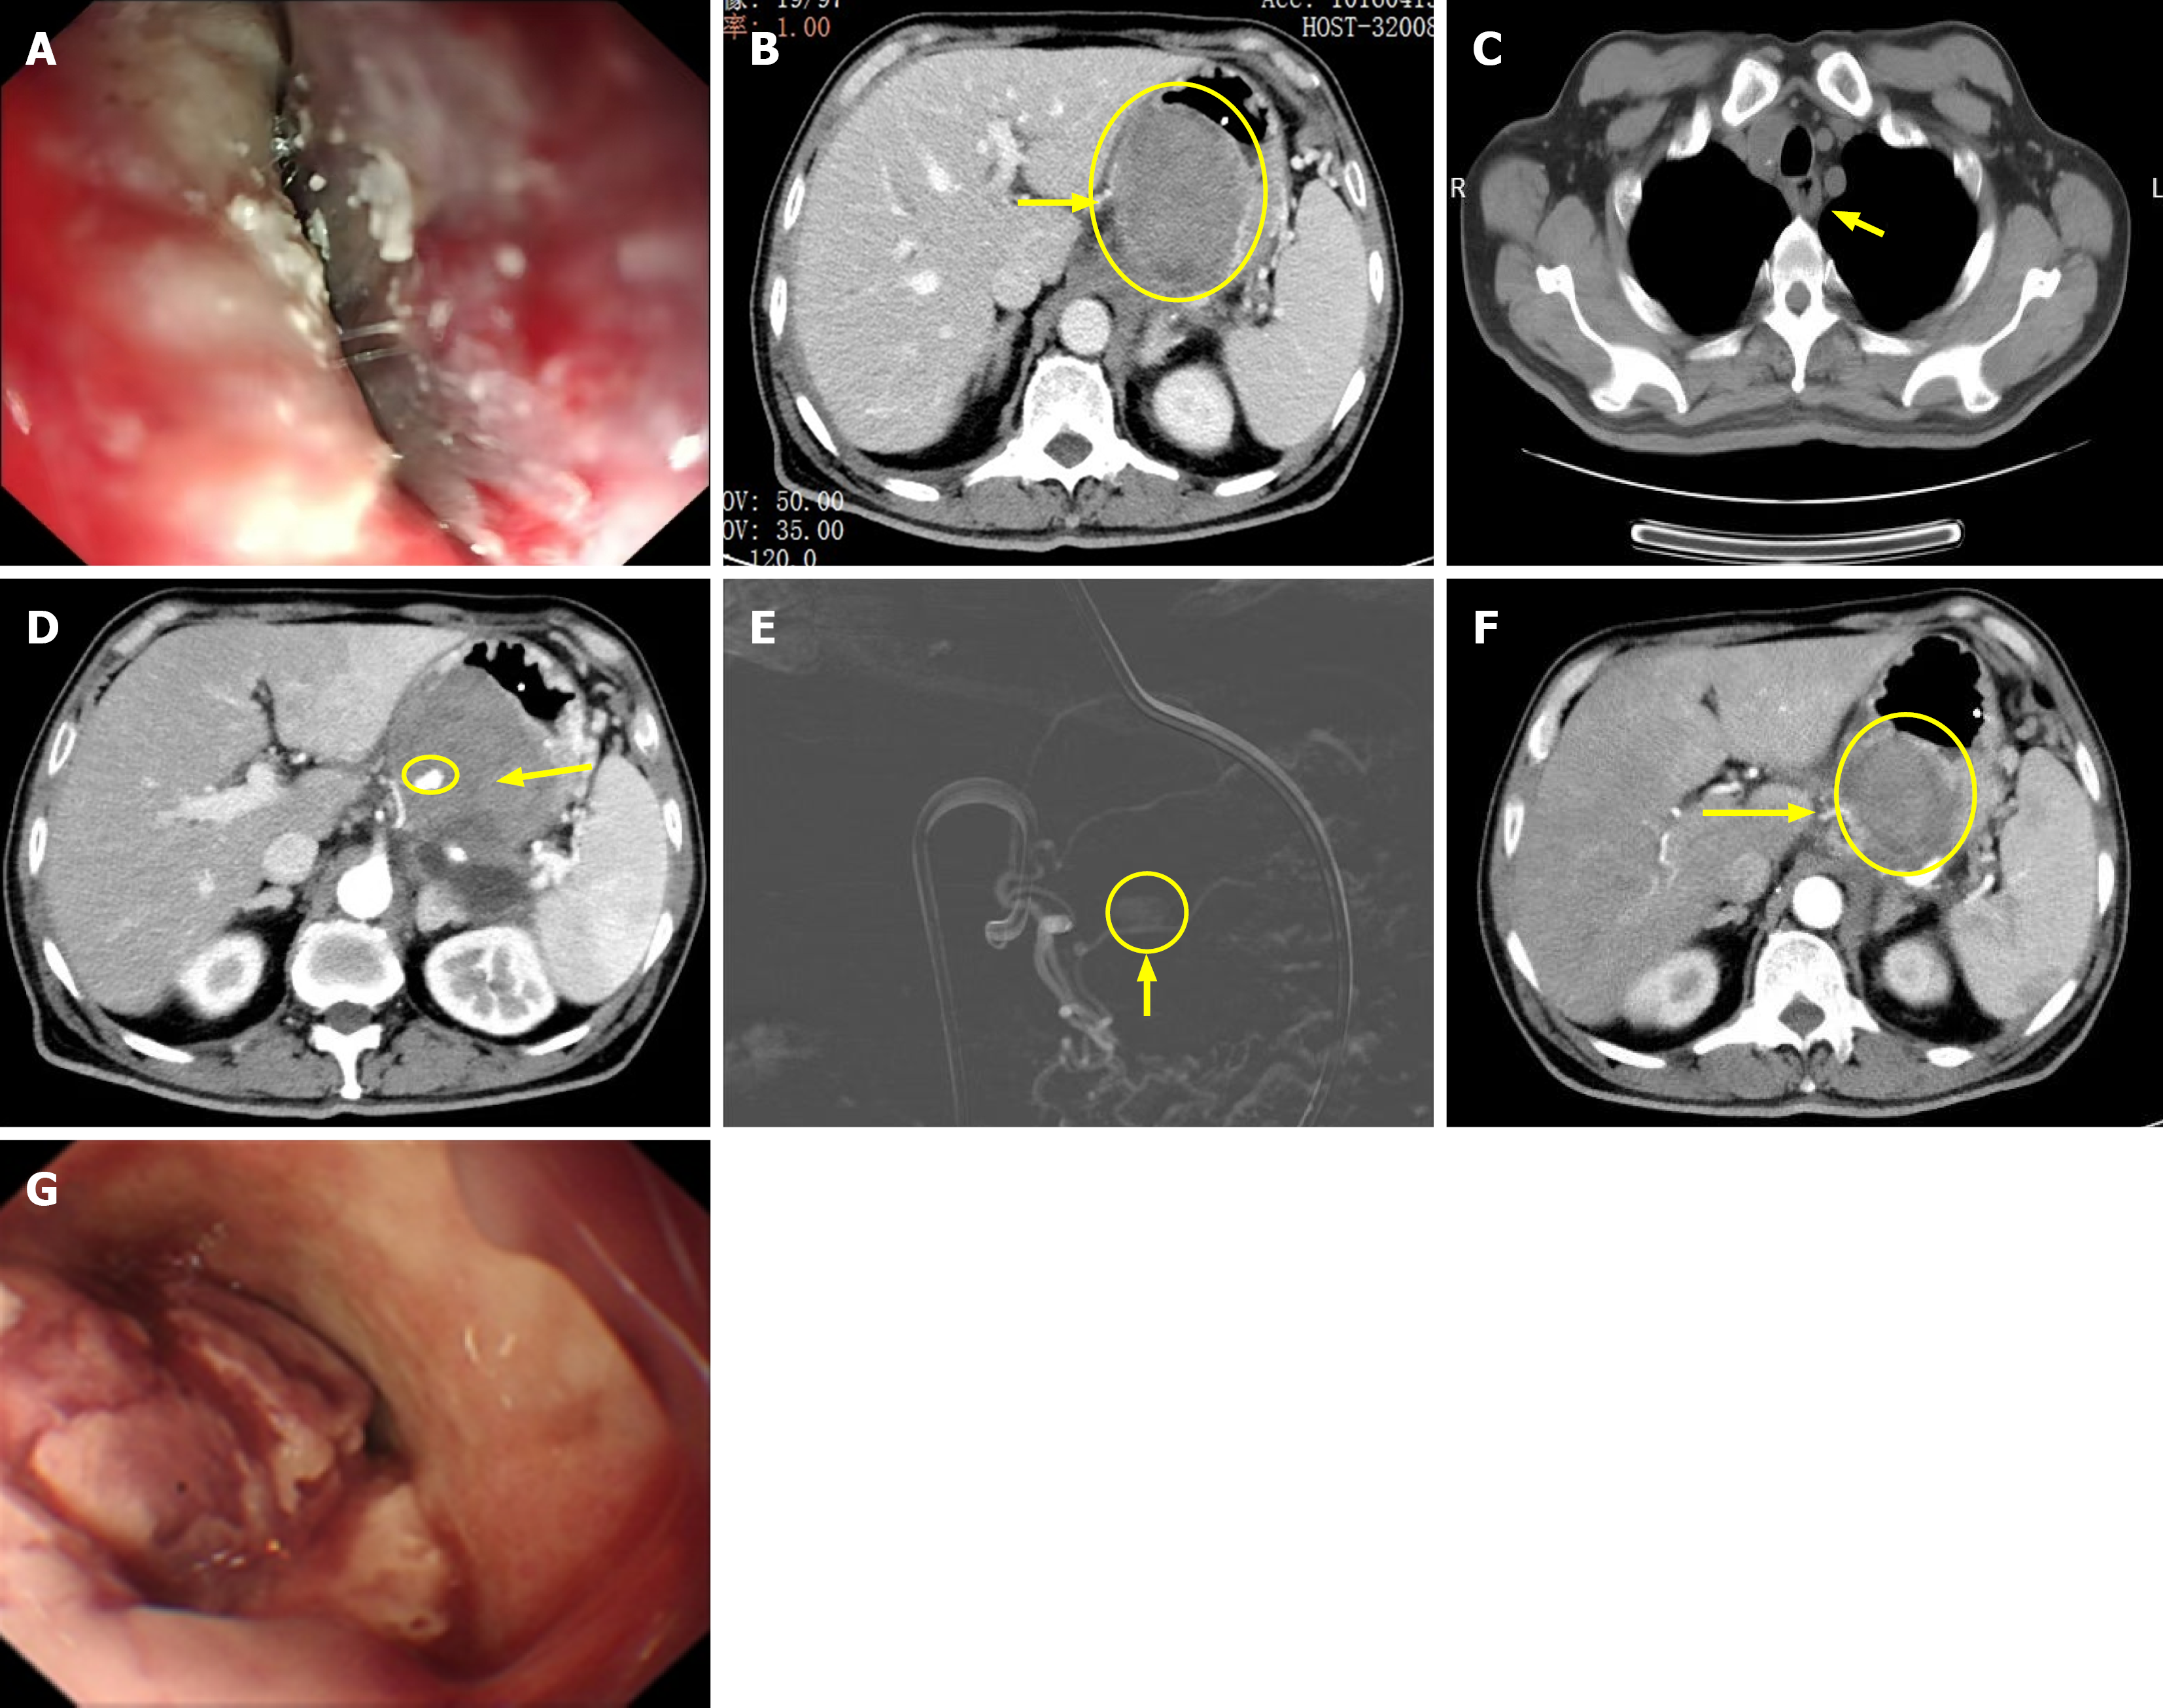

Figure 1 Esophageal and gastric submucosal hematomas.

A: Initial endoscopic image showing esophageal strictures; B: Computed tomography (CT) scan showed a mixed high-density lesion in the small curvature of the gastric body (yellow arrow and circle); C: Submucosal hematoma occupying the esophageal lumen in the lower esophagus (yellow arrow); D: CT scan showed a vascular malformation with active bleeding in a branch of the left gastric artery (yellow arrow and circle); E: Angiography shows thickening and curvature of a branch of the left gastric artery with contrast spillage (yellow arrow and circle); F: Repeat CT scan showed that the hematoma was significantly smaller than before (yellow arrow and circle); G: Repeat endoscopy revealed esophageal hematoma rupture on the surface.